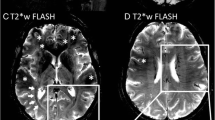

TSPO uptake is increased in MS plaques during relapse [73] (Fig. 3.3) and in some but not all chronic lesions [70, 75], potentially consistent with the “smoldering” inflammation described pathologically in chronic active lesions. Diffuse TSPO binding in NAWM has been shown in RRMS patients compared to healthy controls [76], and may be more pronounced in SPMS compared to RRMS [77]. TSPO uptake in the cortex, cortical lesions, deep GM, and NAWM in MS patients is also associated with worse clinical disability, cognitive function, and more cortical thinning on MRI [77].

MRI and 11C-PBR28 PET images from a patient with relapsing multiple sclerosis. Panels a–c show post-contrast T1-weighted MR images demonstrating an acute lesion that enhances following gadolinium administration (arrows) in sagittal (a), axial (b), and coronal (c) plane. Panels d–f show the corresponding VT (volume of distribution) parametric map demonstrating a focal increase (arrows) in uptake of 11C-PBR28, a second-generation TSPO ligand, perhaps suggesting the presence of activated microglia within these acute lesions. Source images in this figure were previously published and are used with permission [74]